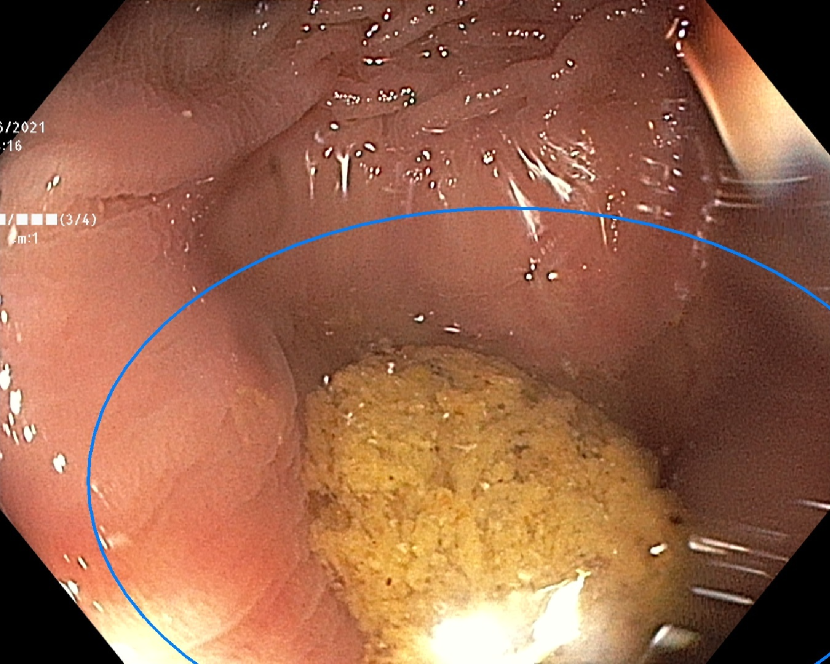

Refer to caption

(b)

Figure 7: Sample images from the testing dataset, with results from the best performing model. White boxes are the ground truth annotations, blue ellipses are the model predictions. In the first row, examples of false negative polyps are shown: (7(a)) a small and distant polyp, (7(b)) a polyp partially covered by water/bubbles, (7(c)) a polyp framed in blue light, (7(d)) a large polyp near the image boundary and overexposed. In the second row, examples of false positive detections are shown: (7(e)) the model activates on a artifact due to stain and motion blur, (7(f)) the model activates on a solid residue, (7(g)) the model activates on an area of the colonic mucosa that is not well inflated, (7(h)) the model activates on a dark and distant area of the colonic mucosa whose shape is similar to a polyp.

Finally, in Figure 7, we display examples of false negatives and false positives from the test set, generated by the best performing model. To visually assess the performance on a whole video, we have uploaded a 60-minute colonoscopy video featuring 6 polyps, the longest in our test set, at https://figshare.com/s/fbb0834a21082984336c (with predictions marked in cyan and ground truth boxes in white). The image examples illustrate how the model struggles with small, occluded, or poorly imaged polyps, and generates false positives in areas that visually resemble polyps, often due to motion or suboptimal imaging. These observations persist throughout the entire video analysis, highlighting the importance of minimizing false positives throughout the entire procedure while maintaining high polyp recall.